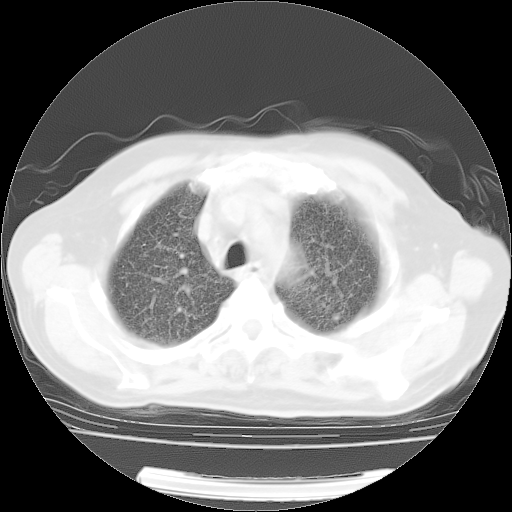

肺部CT平扫未见异常。